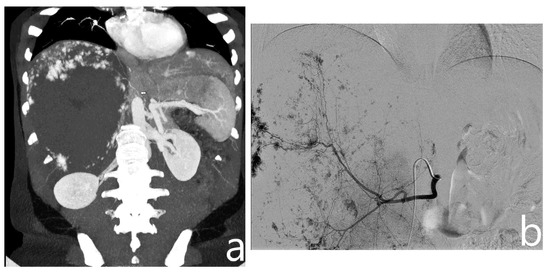

With the patient in the supine position, right femoral access was obtained using a 4F arterial sheath (Terumo Corporation, Tokyo, Japan) with the Seldinger technique. Based on a preoperative CT scan, a 4F catheter (Cordis, Santa Clara, CA, USA), via the arterial sheath, was used to obtain selective angiography of the main arteries involved in the vascularization of the hemangioma (mainly celiac trunk, superior mesenteric artery, and phrenic arteries, Figure 1); if necessary, an aortography was performed using a 4F Pig catheter (Cordis, Santa Clara, CA, USA).

Figure 1.

On preoperative CT (a), a giant hemangioma of the right liver lobe is identified, with evidence of vascular afference from the right phrenic artery (arrow). On angiography, after identification and embolization of the right hepatic artery (b), right phrenic artery is selectively catheterized and embolized with microparticles (c).